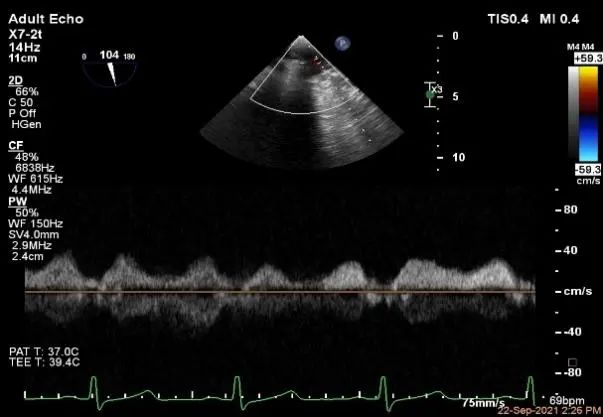

麻醉状态下肺静脉血流频谱

MVA:7.8cm²,平均跨瓣压差:1mmHg

过大鞘

出夹子,建立trajactory

3D调Rotate

夹子进左室

瓣叶捕获后,计算前叶捕获长度9mm,后叶捕获长度7mm。

夹子夹闭后,未见明确残余分流

3d确认夹子位置在P1区

3d-color确认残余分流情况

评估二尖瓣瓣口平均跨瓣压差:1mmHg

肺静脉血流频谱恢复正常